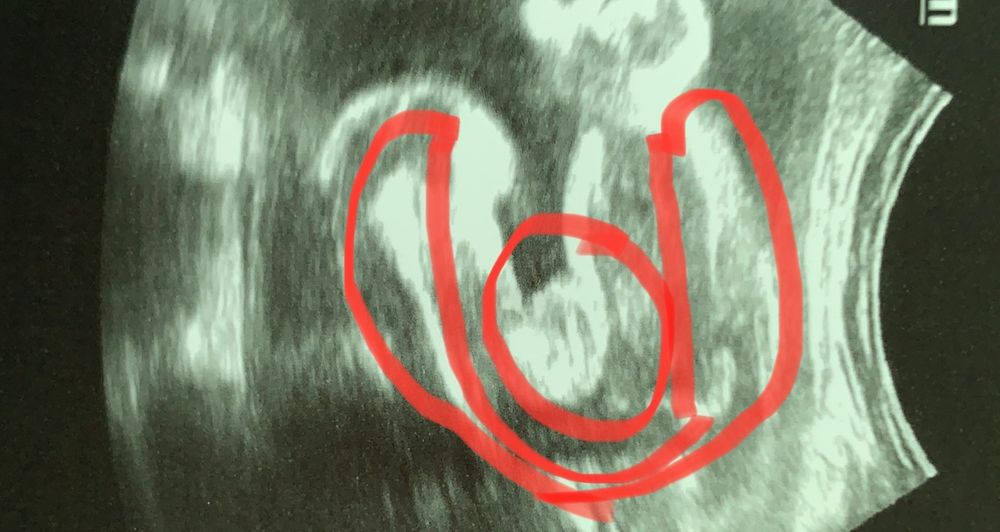

Ольга в Благополучная беременность 3 года Как думаете кто?) Пол малыша Посмотрите еще 20 записей на эту тему Лучший ответ Елена писька 😊 31.03.2023 Ответить Отменить Ответить My life my love Явный же персик 😁 31.03.2023 Ответить Ольга Вот так мальчик может притвориться девочкой ) 31.03.2023 Ответить Ольга Нет мальчик😁оказался 31.03.2023 Ответить Ева Ольга, вот это поворот 😁 я тоже отчетливо увидела девочку) 31.03.2023 Ответить Олеся Ева, и я) 31.03.2023 Ответить Стеша девчонка 31.03.2023 Ответить Ксения Девочка 31.03.2023 Ответить Соня девочка. на кофейное зёрнышко похоже 31.03.2023 Ответить Катя Катерина Ну если на фото гениталии - должно быть девочка) 31.03.2023 Ответить 7-8 недель первый скрининг, пол Чаты Беременных Выберите чат: Январята-2026 Февралята-2026 Мартята-2026 Апрелята-2026 Майчата-2026 Июнята-2026 Июлята-2026 Августята-2026